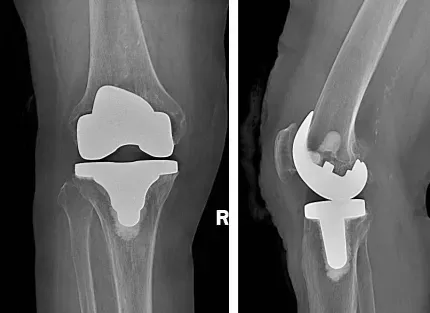

术前准备完善后,北京大学第三医院关节外科专家赵旻暐主任医师来到我院,通过术中定位、截骨、试模、安装膝关节假体等一系列复杂操作,为两位患者先后实施了单侧人工全膝关节表面置换术。由于手术切口较小,疼痛较轻,术后第一天,他们便在医生指导下,手扶助行器迈出了意义非凡的“第一步”。看到患者术后恢复的这么好,家属脸上露出了满意的笑容,对北京专家的诊疗技术称赞不已。

人工膝关节置换术作为膝关节骨性关节炎治疗的手术方法,随着对膝关节生物力学研究的不断深入,膝关节假体设计理念不断更新,人工膝关节置换手术也日趋成熟,通过采用高分子聚乙烯和金属等假体置换受损的关节,可重建膝关节解剖结构,恢复生理解剖构造,对于恢复患者正常行走能力,改善膝关节功能,提升生活质量,有着重要的意义。